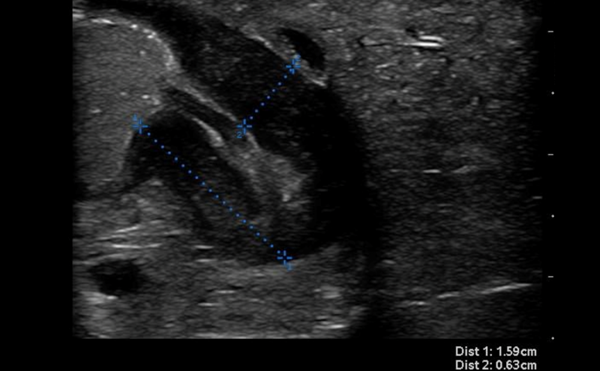

Advanced ultrasound can enhance the diagnosis of organ injury, viable tumor, and vascular pathologies at bedside.

Small Parts - Testicular Ultrasound